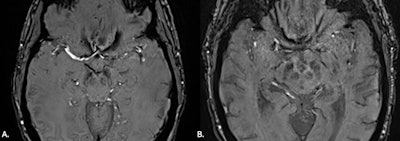

(A) MRI brain SWI axial scan shows normal appearance of nigrosome-1, high signal in a linear shape within the substantia nigra. Also known as swallow tail sign. (B) MRI brain SWI axial: substantia nigra signal intensity reduced bilaterally, with loss of the hyperintense signal in nigrosome-1 in keeping with loss of swallow tail sign, which may reflect Parkinson’s disease.